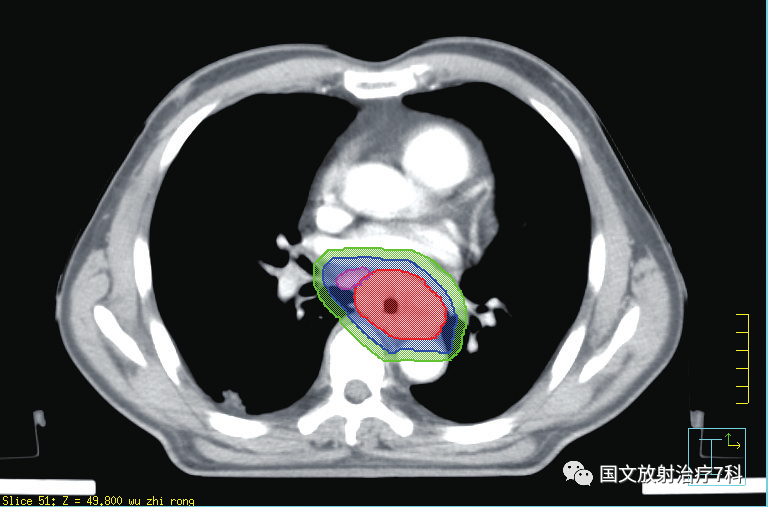

第三步,勾畫靶區(qū)之后,醫(yī)生需要提交治療計劃,與醫(yī)學(xué)物理師共同完成對靶區(qū)劑量的設(shè)定,以及危及器官受量的限定。物理師需要借助電腦軟件精確腫瘤患者的放療物理范圍,獲得最優(yōu)的物理劑量分布,做出一個讓放療醫(yī)生滿意的放射治療方案,為腫瘤患者“對癥下藥”。 簡單來講,就是讓射線最大量的照射在靶區(qū)上,最大程度地控制周邊需要保護(hù)器官的射線劑量。靶區(qū)勾畫和治療計劃確認(rèn)依病情的復(fù)雜程度一般需要3-7天,需要患者的耐心等待。醫(yī)學(xué)物理師是臨床醫(yī)師和大型精密治療器械的銜接單位,有強(qiáng)大的醫(yī)學(xué)物理師團(tuán)隊是對治療的充分保障。